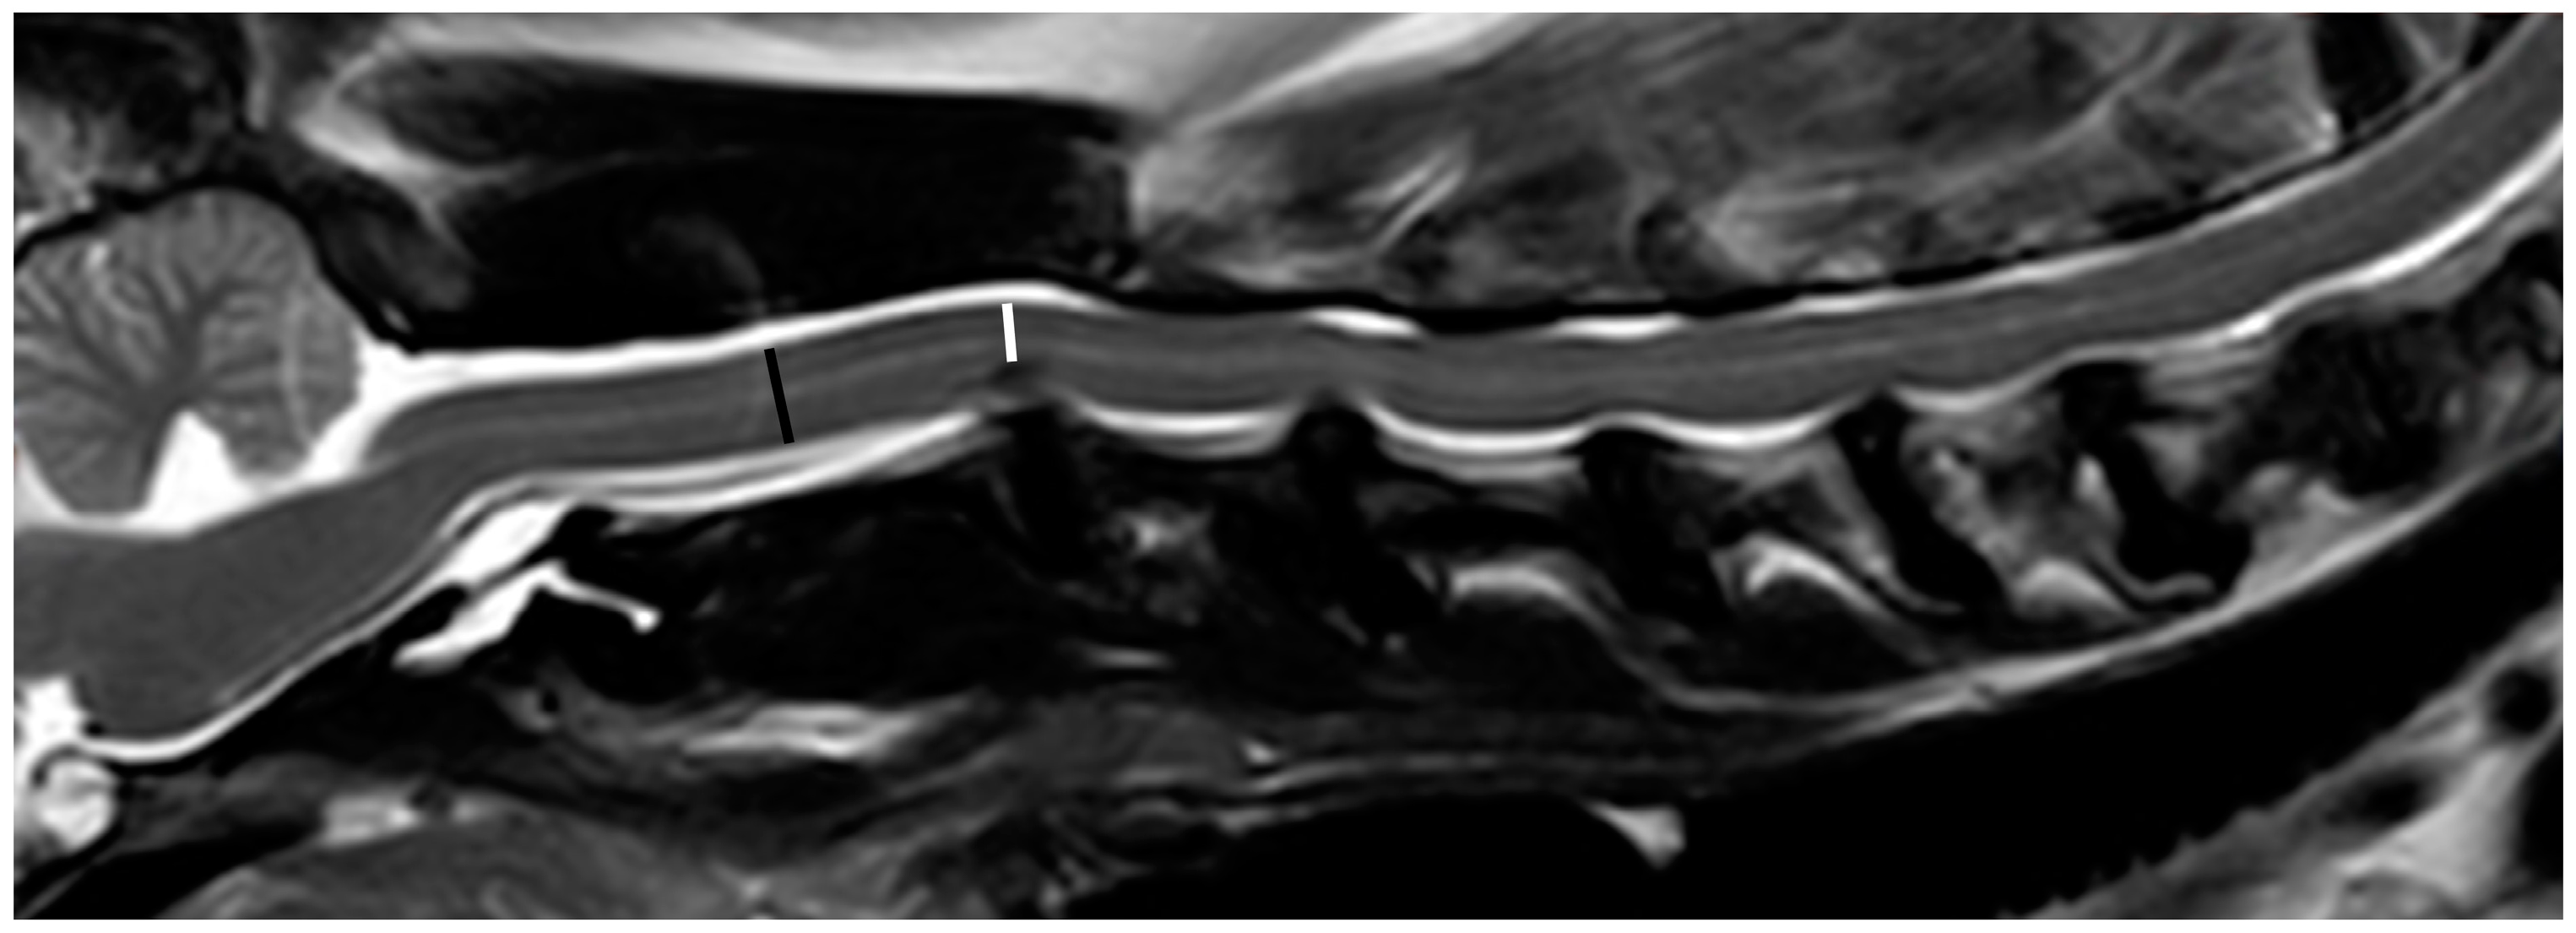

A single examiner (YPC) reviewed all images and performed all measurements (RadiAnt DICOM Viewer 2021.2, Medixant, Poznan, Poland). The severity of spinal cord compression at each extruded or protruded disc was determined. All measurements were repeated three times to obtain the mean values. Owing to the imaging quality of the 0.2 T MRI, accurately measuring the spinal cord area in transverse T2-weighted images was considered difficult. Therefore, spinal cord compression was determined by measuring the spinal cord height (SCH) in the midline sagittal T2-weighted image by the following formula [16,28], if there was mainly ventral spinal compression (Figure 1):

Figure 1.

Midline sagittal T2-weighted image obtained with a 1.5 T MRI demonstrating measurement of spinal cord compression at the C2/C3 disc. The black line represents the spinal cord height at the middle level of the C2 vertebra, and the white line represents the spinal cord height under maximal compression at the C2/C3 disc. The spinal cord compression at C2/C3 disc is measured as 35%, classified as moderate severity.

For lateralized disc herniation, the measurement was conducted using the transverse T2-weighted images only if the transverse images were perpendicular to the long axis of the spinal cord and the transverse image at the mid-level of the cranial vertebra was available. Otherwise, the dogs were excluded from the study. For each IVDE or IVDP, the severity of spinal cord compression was further categorized using a grading system: mild, <25%; moderate, 25 to <50%; and severe, ≥50%.